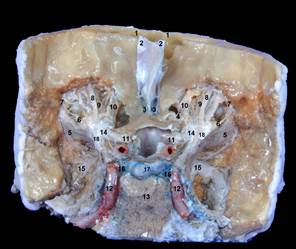

Рис. IMG_3958_номерки